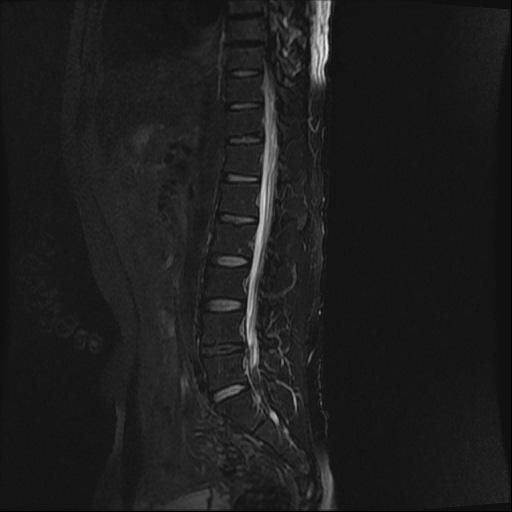

강직성척추염 의심(xray 및 mri 첨부)

인터넷 검색 후 강직성척추염을 알게 되어 말씀 드렸더니 스트레칭??을 해보시고 아닌 것 같은데 걱정이 된다고 하니 x-ray 및 mri를 찍어보자고 하셨습니다. (유전자검사는 채혈 후 대기 중)

xray 및 mri상에도 의심소견이 없다고 하셨는데

사진으로 염증이 있는지 확인 부탁드립니다.

강직성척추염과같은 염증성질환의경우 엑스레이로만은 확인하기가 어려운데요 다른 인자검사라던가 정확한 진단을위한 MRI검사등이 필요할수있습니다

올려주신 엑스레이나 MRI를 참고할 때, 또는 진료시 스트레칭을 통한 허리 및 천장관절의 유연선 평가와 개인에 따라 다르지만 대표적인 강직성 척추염의 증상이 크게 없는 것으로 보아 발생 가능성이 낮을 수 있습니다.

강직성 척추염은 주로 허리의 움직임 제한 및 영상검사에서 관절염에 해당하는 소견과, 혈액검사등에서 염증수치가 증가되어있는 경우가 많지만 이에 해당하지 않는다면 가능성은 낮다고 볼 수 있습니다.